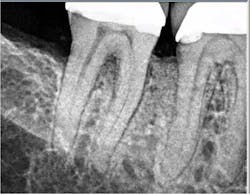

In the present case, a 61-year-old male was referred to my periodontal office by his general dentist for an evaluation of pain and bleeding to the lower right mandible. The patient’s medical history consisted of controlled type 2 (noninsulin dependent) diabetes and hypertension. Upon review of the panoramic radiograph (figure 1), the periodontal defects are not clearly evident, thus showing the importance of proper radiographs to detect periodontal defects. The periapical radiographs (figure 2) clearly show subgingival calculus, grade 1 furcation on No. 30, grade 3 furcation on No. 31, and an advanced intrabony defect on the distal of No. 30. Clinically, there was no mobility to either No. 30 or 31 and both teeth were vital. Tooth vitality is an extremely important diagnostic factor in treatment panning. Periodontal charting of the lower right was also performed, and the lower right exhibited bleeding and inflammation (figure 3).

The patient returned for a postop appointment at 5.5 months and a new radiograph (figure 5) and clinical photographs (figures 6 and 7) were taken. Excellent regeneration is evident at both sites radiographically and clinically. New periodontal charting was done (figure 8) showing near-complete regeneration of the intrabony defect on the distal of No. 30 and a great improvement in the furcation of No. 31. There is no bleeding or inflammation present at this time.